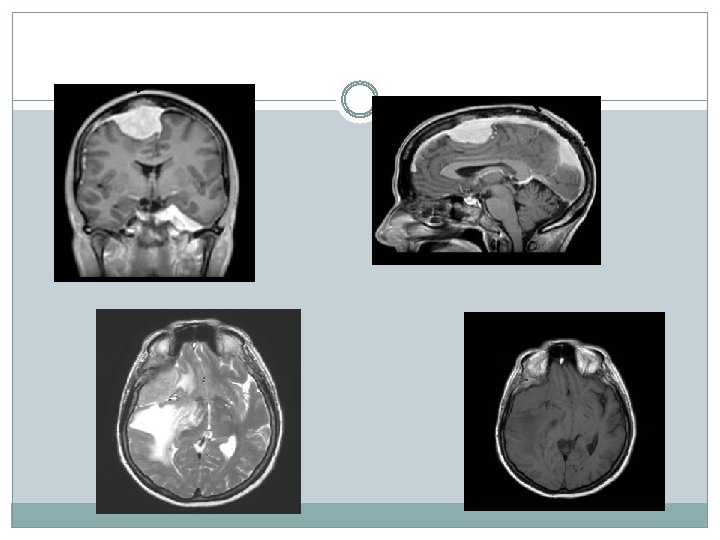

Examen IRM spinale et encéphalique: Séquences T 1, T 1 gado 3 D, FLAIR, T 2 en coupe sagittale et axial Cytologie du LCR Recher des signes d’extension méningée

Examen T 1 coupe axial

Examen